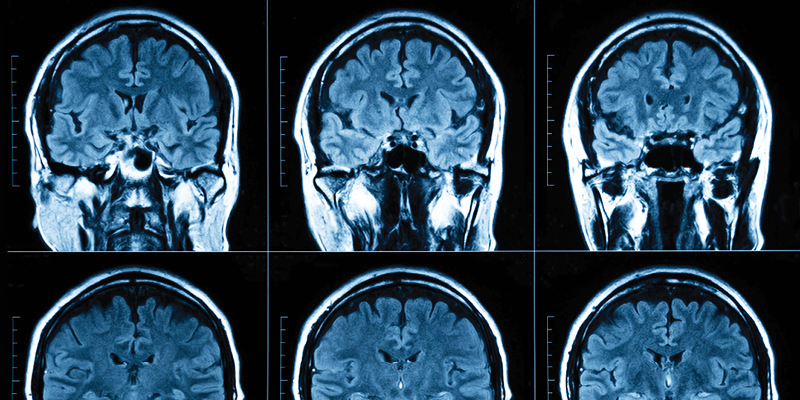

Making the Science of the Brain Reliable and Reproducible

How Differences in Processing Reliability Can Hinder Advancement in Neuroimaging

Examining how cross-tool differences can distort our ability to detect individual variations, and advance the field.

Computational Errors Could Have a Negative Impact on the Ability to Study Brain Networks

Identifying the effects that random unavoidable computing errors have on developing reliable models of brain-phenotype relationships.